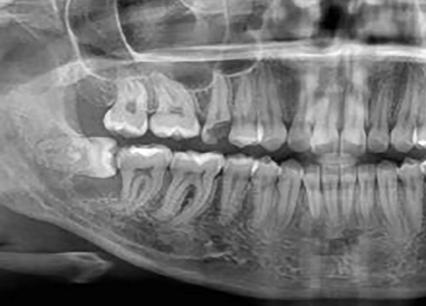

El examen radiológico reveló una imagen radiolúcida bien circunscrita alrededor de la raíz distal del segundo molar inferior (47), asociada al diente incluido en posición horizontal. Figura 1. Con base en los hallazgos clínicos y radiográficos, se estableció la hipótesis diagnóstica de quiste dentígero asociado al diente 48.

Figura 1: Radiografia panoramica evidenciando un área radiolúcida bien delimitada envolviendo a corona de diente (48), que se encontraba em posicion horizontal, em intima relacion com la raiz del diente (47).